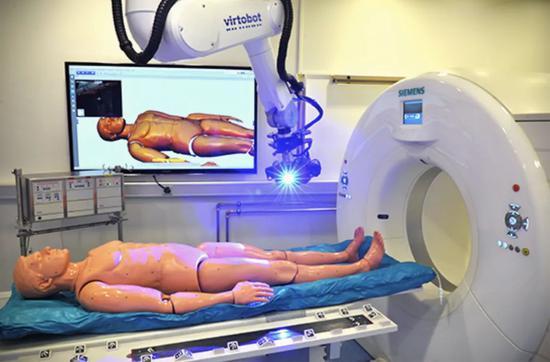

虚拟尸检是由以虚拟化、数字化的形式替代手术式尸体解剖。丨thalheimer-kuhlung.com

虚拟尸检仪器Virtobot